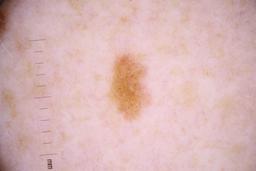

ISIC_4077341

Clinical

| Field | Value |

|---|---|

| acquisition_day | 1 |

| age_approx | 50 |

| anatom_site_1 | Trunk |

| anatom_site_2 | Anterior trunk |

| concomitant_biopsy | False |

| dermoscopic_type | contact non-polarized |

| diagnosis_1 | Benign |

| diagnosis_confirm_type | serial imaging showing no change |

| family_hx_mm | False |

| image_type | dermoscopic |

| lesion_id | IL_9238622 |

| patient_id | IP_1969685 |

| personal_hx_mm | True |

| sex | male |